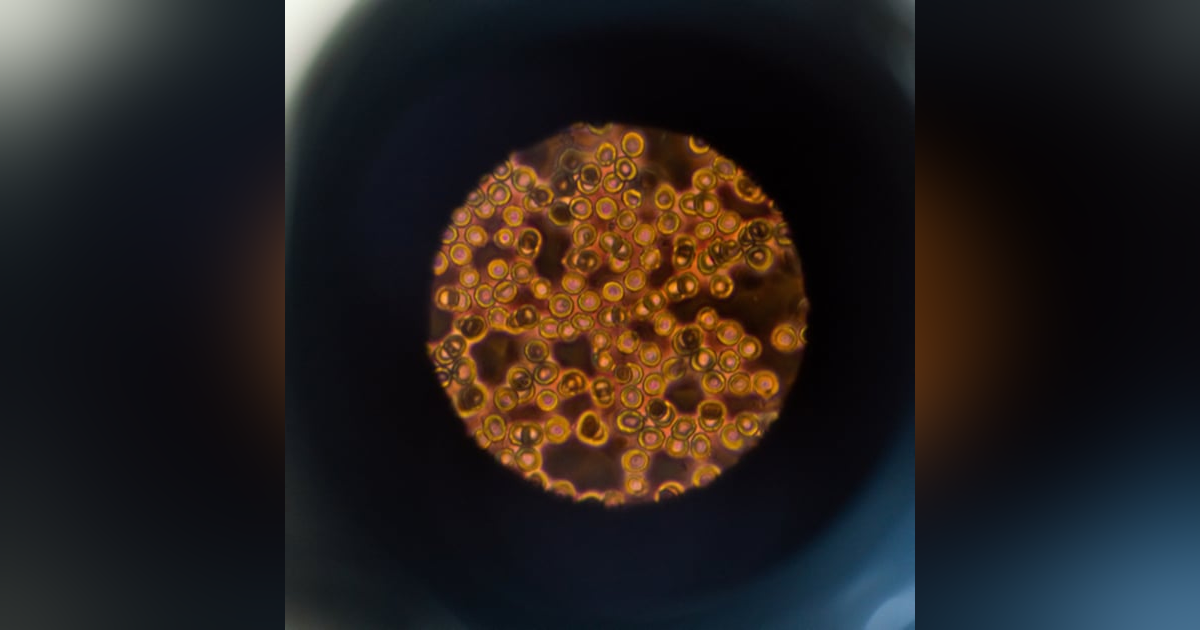

In our two-part series on coagulation, we talk to Prof. Bruce Parry, a former clinical pathologist from the University of Melbourne. In part 1 we cover primary coagulation. We talk everything platelets: how to accurately pick cases of thrombocytopaenia, pro-tips to make sure you get to the right answers, and common pitfalls. We also look at the buccal mucosal bleeding time test: how to do it, and what information it will provide.